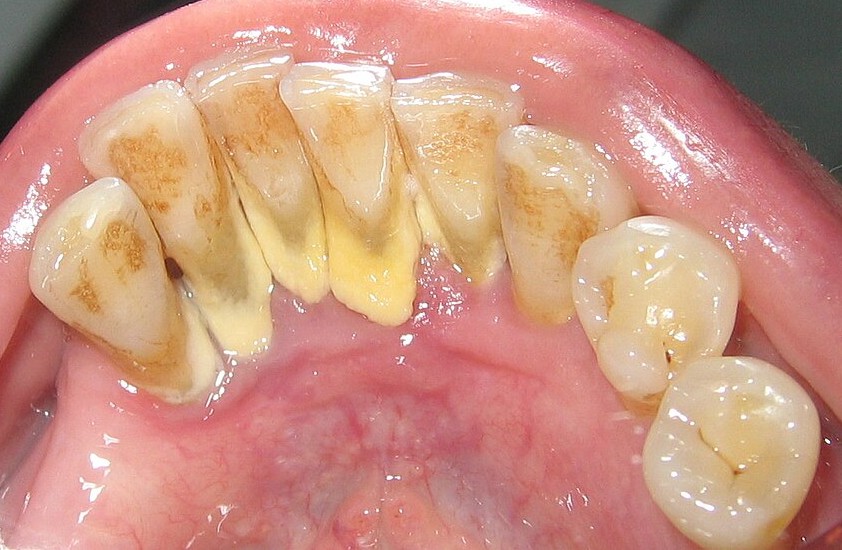

Now, let’s take a deep dive into calculus bridges. What they are, how they form, and the problems that can result from unchecked tartar buildup. Below, you’ll also find calculus bridge images that will give you some perspective on how these issues can present, and whether the problems you’re facing are calculus or something else. We’ll also include some pictures of calculus teeth before and after to demonstrate how these issues can progress rather quickly.

What Does a Calculus Bridge Look Like?

Patients with a calculus bridge will see a solid, off-white/yellow layer that often covers the gaps between their teeth. It often appears brown as well. A calculus bridge may even cover the gum line, extending above the teeth line in ways that can make your teeth appear misshapen or misaligned.

However, you may know a drastic color change as a calculus bridge grows and tartar buildup increases. While it can initially appear yellow, long-standing calculus bridges will often appear green, dark brown, or even black in more serious cases. This is due to an increased buildup of organic matter on top of the bridge layer. While food is a common factor, red wine, coffee, and tobacco are other triggers for teeth darkening.